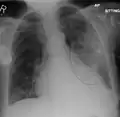

AP CXR showing left lower lobe pneumonia associated with a small left sided pleural effusion

AP CXR showing right lower lobe pneumonia